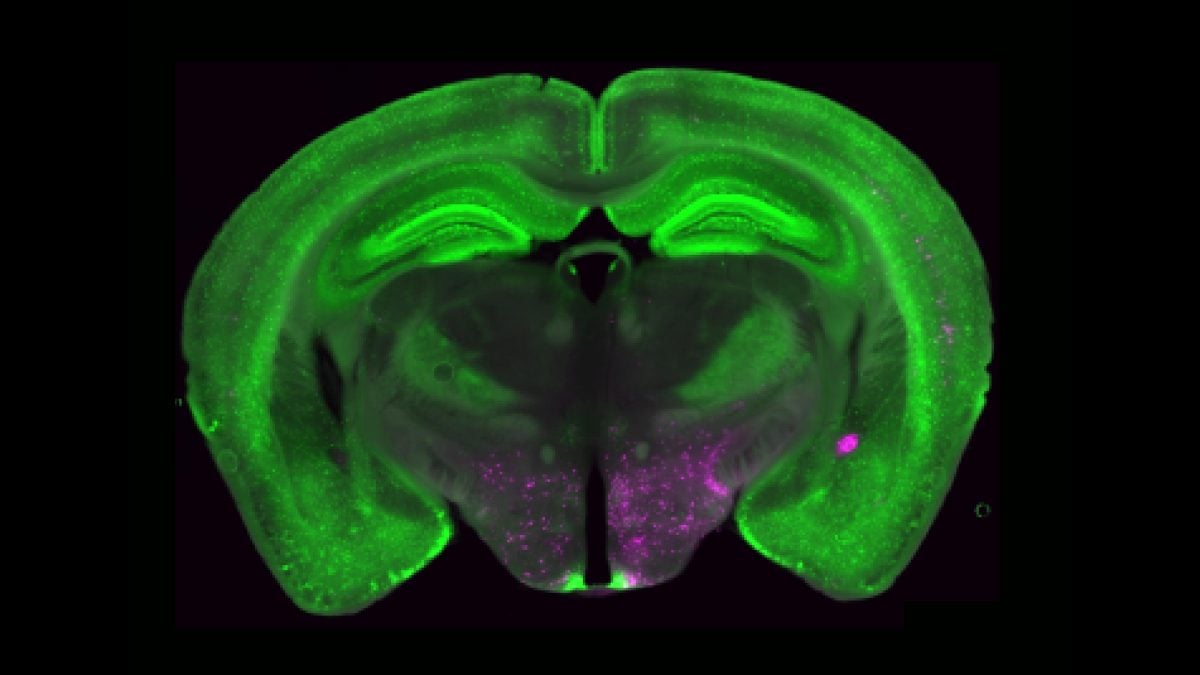

Флуоресцентні зображення NPY+ нейронів (зеленого кольору) по всьому мозку показані на додаток до нейронів пурпурного кольору, які надсилають проекції до PBN. Зображення: J Ніколас Бетлі

Структурно Y1R-нейрони розкидані серед інших типів клітин, що ускладнює їх точне картування. Бетлі порівнює це з мозаїкою: «Ми очікували, що це будуть жовті автомобілі, припарковані разом, але натомість побачили жовту фарбу, розкидану між червоними, синіми і зеленими». Такий розподіл може бути стратегічним, дозволяючи впливати на різні сенсорні шляхи болю одночасно.